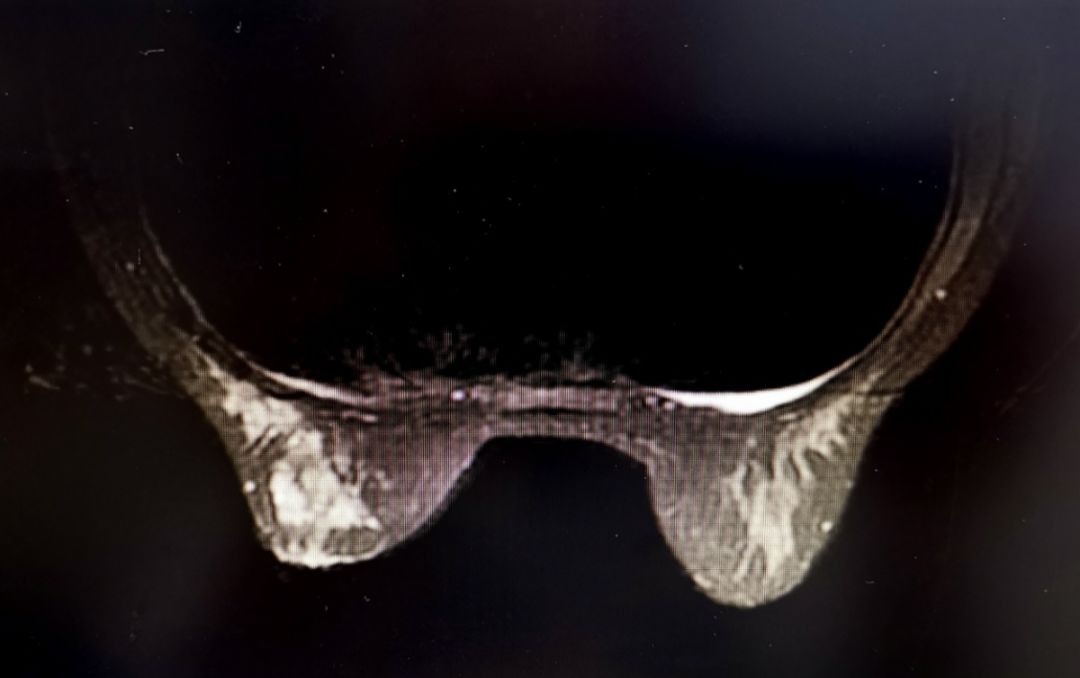

彩超:左乳中央腺体层可见大小约 4.10 cm* 1.80 cm的低回声团块,边界不清,边缘毛糙,其内回声分布不均匀,CDFI示血流信号III级。双侧腋窝及双侧锁骨上下未见明显肿大的淋巴结。彩超提示:1. 左乳外上及内上低回声团块,BI-RADS-US 4a类。

图1 乳腺超声检查